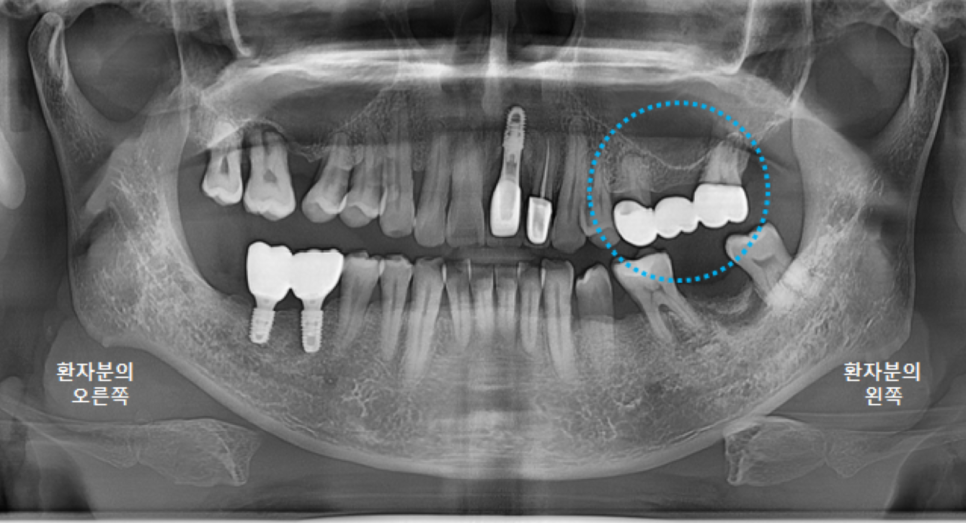

보철물을 다 붙이고 나서 촬영한 파노라마 엑스레이입니다.

앞니가 들어가서 심미적으로도 좋아졌고,

교합 평면도 좋아졌습니다.

이제 환자분의 식사가 조금 더 편해져서, 잘 드실 수 있게 되었습니다. ^^